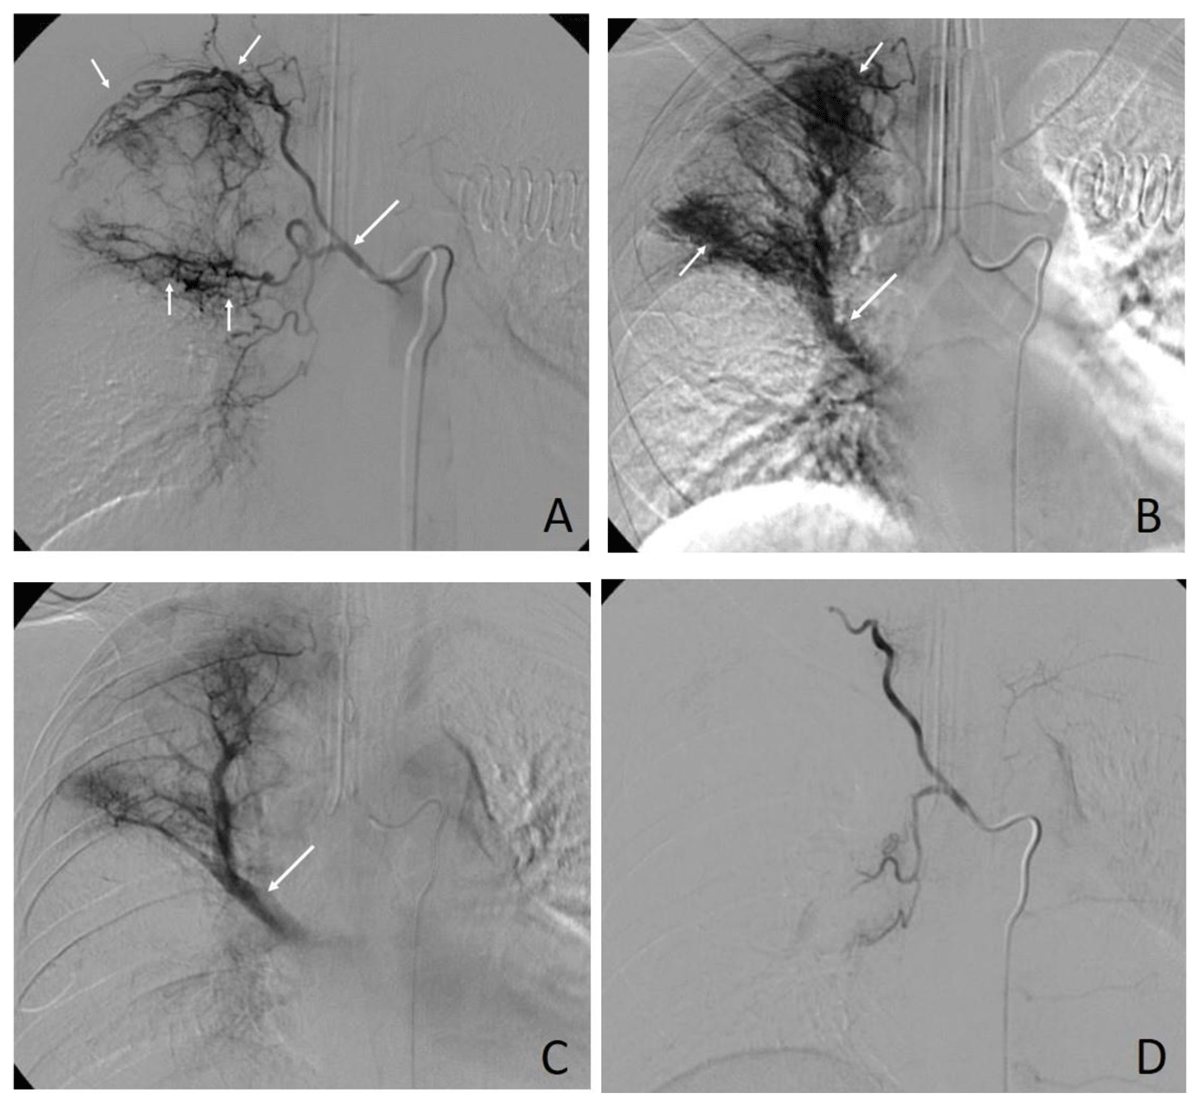

Table 2 presents the detail of angiographies and embolizations. The most commonly encountered abnormalities on angiographies were hypervascularity of lung parenchyma (95.7%) (Figure 1). Pseudoaneurysm was found in 3.3%, and contrast extravasation was seen only in 1.1%. Technical success rate was found in 170/184 (92.4%) procedures. The PVA was the most common used embolic agent (58.7%). Clinical success was achieved in 129 procedures (70.1%). Recurrent hemoptysis was found in almost half of the procedures. The overall complication rate was 6.0%. Almost all of them were minor complications. The major complication was seen in one case, in which the patient presented with bilateral lower limb paraplegia and paresthesia, which likely to have occurred due to anterior cord ischemia. There was no BAE-related death in this study.

Figure 1

A 54-year-old male patient with a history of old pulmonary tuberculosis. (A) Selective right intercostobronchial angiography showing hypervascularity of lung parenchyma at the right upper lobe (small arrows) feeding from the dilated right intercostobronchial artery (large arrow). (B) Parenchymal and (C) delayed phases of angiographies showing obvious hypervascularity of lung parenchyma (small arrows in B) and shunting draining to the upper lobe branch of the right pulmonary vein (large arrows in B and C). (D) An angiogram after embolization with polyvinyl alcohol showing complete occlusion of right intercostal and bronchial arteries.